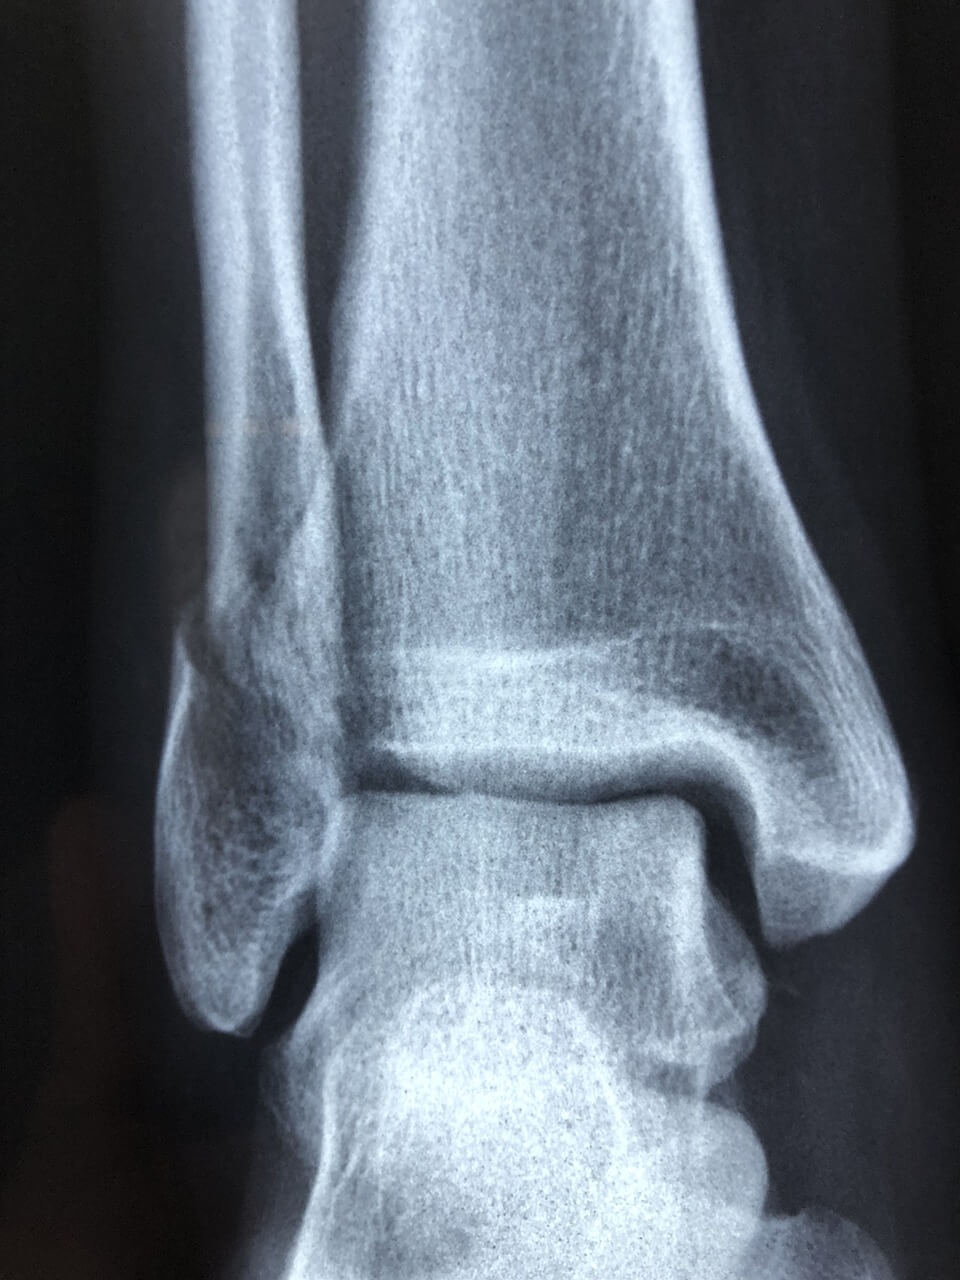

많은 사람들이 발목 염좌와 골절을 혼동합니다. 염좌는 일정 시간이 지나면 보행이 어느 정도 가능하지만, 골절은 체중 부하 자체가 불가능하고 뼈의 모양이 변형될 수 있습니다. 정확한 구분을 위해서는 X-ray나 MRI 검사가 필요합니다.

- X-ray: 골절 여부를 확인하는 기본 검사.

- MRI: 인대 파열 정도, 연골 손상 여부를 정밀하게 확인.

- 초음파: 실시간으로 인대 상태를 관찰할 수 있으며, 재활 단계 평가에도 유용합니다.

발목 염좌는 골절이나 연골 손상과 함께 동반되는 경우가 있어, 단순한 ‘삐끗함’으로 단정하지 말고 정확한 검사가 필요합니다.